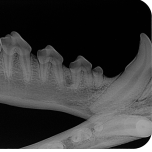

Discover underlying pathology, increase workflow efficiency with wider clinical application, only achievable with iM3’s large format size 4 and size 5 high resolution dental image plates.

Excellent quality and superior high resolution (25lp/mm) images via Vet Exam software